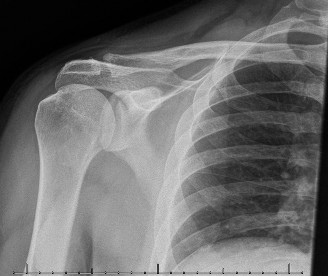

Rotator cuff tears are a common reason for shoulder pain and a common reason to obtain shoulder imaging. As a result, numerous different imaging modalities exist offering different pros and cons. Plain films are still the initial imaging modality of choice. These are most useful in ruling out other possible diagnosis but can help with the diagnosis of a rotator cuff tear as well. Changes to the tendon itself

may appear as calcific tendinosis, which would most commonly be seen at the bone–tendon interface. A decrease in the acromiohumeral distance (less than 2 mm) may also be indicative of a cuff tear. In late cases of rotator cuff tears, superior subluxation of the humerus may be evident. Certain variations in acromial anatomy, including spurs or a hook-shaped (type 3) acromions, may be associated with rotator cuff tears as well. With progression of rotator cuff tears, degenerative changes including spurs, cysts, and sclerosis may be evident at the greater tuberosity. In late, massive tears one may see degenerative changes consistent with rotator cuff arthropathy.